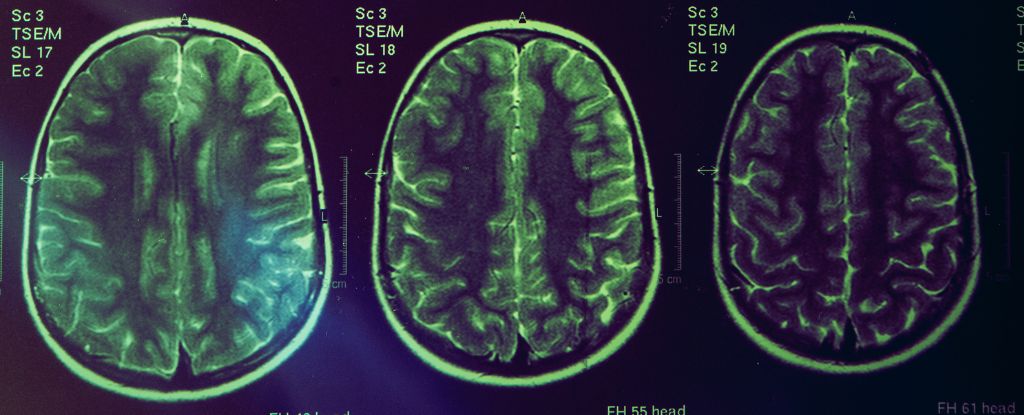

Alzheimer’s Reimagined as an Immune-System Brain Disorder

The piece argues Alzheimer's may be primarily an autoimmune disorder of the brain rather than just a brain disease, challenging the traditional beta-amyloid focus and the controversial aducanumab approval. It posits beta-amyloid may be part of the brain’s immune response that goes awry, driving dementia, while other theories (mitochondrial dysfunction, infections, metal handling) gain traction. With Alzheimer's affecting tens of millions worldwide, the article calls for new immune- and mechanism-based therapies and directions.